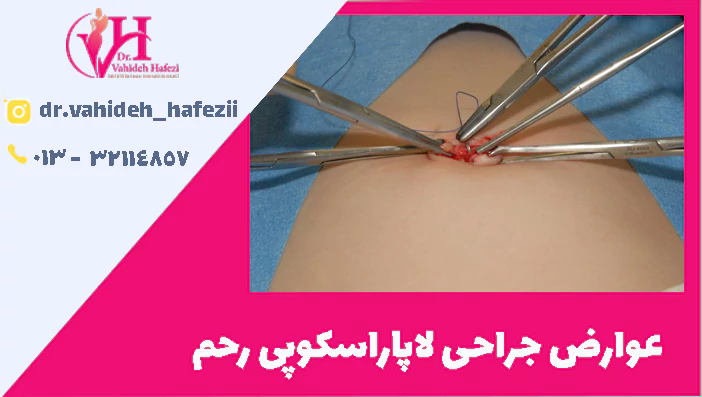

از عوارض جراحی لاپاراسکوپی رحم، عفونت در محل زخم

هرچند لاپاراسکوپی روشی کمتهاجمی است، اما عفونت در محل ورود ابزارها به بدن همچنان یکی از عوارض جراحی لاپاراسکوپی رحم به شمار میرود. قرمزی، تورم، درد یا ترشح از محل برشها میتواند نشانه بروز عفونت باشد. در موارد شدیدتر، ممکن است بیمار به آنتیبیوتیک یا حتی بستری مجدد نیاز داشته باشد. رعایت کامل بهداشت و پیروی دقیق از دستورات پزشک در دوران نقاهت، احتمال بروز این عارضه را کاهش میدهد.